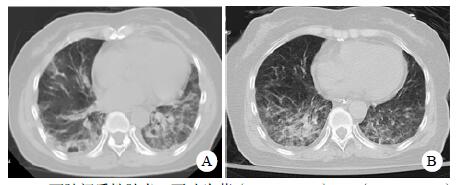

患者,女,54岁,工人,因“头晕5 d”于2019年9月29日至浙江大学附属第二医院急诊就诊。5 d前患者无明显诱因出现头晕,伴行走不稳、四肢乏力,无发热、咳嗽咳痰、胸闷气促、恶心呕吐、四肢抽搐等,未就诊。我院急诊头颅磁共振(MRI)示:右侧丘脑及左侧岛叶异常信号,局部累及右侧中脑(图 1),考虑脑多发占位性疾病。在急诊抢救室予甘露醇100 mL静滴脱水降颅压等对症治疗,5 h后患者逐渐意识模糊。急查血常规:白细胞16.1×109/L,中性粒细胞百分比73.4%;头颅CT示右侧丘脑、左侧岛叶病变,伴脑室扩张(图 2);急诊行“双侧脑室外引流术”,术中引流液呈淡血性。术后诊断:⑴(右侧丘脑)颅内占位性病变,脓肿首先考虑,肿瘤需排除;⑵脑积水;⑶脑疝。患者带气管插管转入ICU进一步治疗。当时体温38.3℃,脉搏99次/min,呼吸频率24次/min,血压169/87 mmHg(1 mmHg= 0.133 kPa),颈软,神志昏迷,右侧瞳孔3 mm,左侧瞳孔2.5 mm,对光反射迟钝。双肺呼吸音粗,可闻及少量啰音。左侧病理征阳性。患者3个月前曾因“反复胸闷气促伴发热1个月余”在本院风湿科住院,当时胸部高分辨CT示两肺间质性肺炎、下叶为著(图 3);血化验示血沉偏高,抗心磷脂抗体阳性;诊断为“间质性肺炎”,住院期间予甲泼尼龙40 mg/d静滴×8 d,60 mg/d静滴×6 d,共住院14 d;出院后予口服甲泼尼龙40 mg/d联合雷公藤多苷片每次20 mg,一日2次治疗;此后规范于本院门诊复诊。本次起病前2个月甲泼尼龙已减量至36 mg/d口服治疗。

| A:两肺间质性肺炎,下叶为著(2019-06-23);B:(2019-09-30)两肺间质性肺炎,下叶为著,较前(2019-06-23)部分好转 图 3 患者胸部HRCT结果 |

转入ICU后呼吸机辅助通气、甘露醇100 mL/8 h静滴脱水、头孢呋辛1.5 g/12 h静滴抗感染,肠内营养等支持治疗。当晚血常规:白细胞13.3×109/L,中性粒细胞百分比85.3%,C反应蛋白17.1 mg/L,降钙素原0.64 ng/mL。脑室外引流术后次日血化验:白细胞16.6×109/L,中性粒细胞百分比92.8%,C反应蛋白78.4 mg/L;从脑室外引流管留取脑脊液检验:有核细胞6×106/L,红细胞1 960×106/L,蛋白含量1.717 g/L,葡萄糖4.72 mmol/L,细菌培养阴性,涂片未找到细菌;复查头颅CT示:脑室扩张好转,右侧丘脑、左侧岛叶病变伴出血(图 2);胸部CT示,两肺间质性肺炎下叶为著,较前(2019年6月21日)部分好转(图 3)。考虑到炎症指标升高,遂改哌拉西林他唑巴坦3.375 g/12 h静滴抗感染。此后经脑室外引流管反复留取脑脊液送检涂片及培养均阴性。术后第5天行“导航下立体定向颅内病灶活检术+双侧omaya囊置入术”,术中穿刺液呈黄色黏稠脓性,考虑脑脓肿,留取脓液送高通量测序(next-generation sequencing, NGS),并升级为美罗培南2 g/8 h联合利奈唑胺0.6 g/12 h静滴抗感染治疗。术后第7天患者突发血压升高、瞳孔不等大,昏迷程度加深;急查头颅CT示,双侧脑室钻孔引流术后改变,双侧侧脑室引流管走形区出血伴血肿形成;右侧丘脑区积液、积血,双侧脑室积血新发(图 4),甘露醇加量至250 mL/8 h联合地塞米松5 mg/6 h静滴加强脱水;当日术中脓液高通量测序结果回报:皮疽诺卡菌(序列数52 867个)、支气管戈登菌(序列数10个)。确诊脑诺卡菌病,抗菌治疗方案改为亚胺培南西司他丁0.5 g/6 h静滴,联合利奈唑胺0.6 g/12 h和复方磺胺甲恶唑片(0.48 g/片)3片/6 h口服。此后患者仍伴低热,炎症指标呈上升趋势。术后2周患者再次突发血压升高、瞳孔不等大、对光反射消失、神志深昏迷,急查头颅CT示再发脑疝(图 5),急诊行“去骨瓣减压术+脑内血肿清除术”,术后患者仍呈深昏迷状态,双侧瞳孔散大、对光反射消失,次日自动出院。